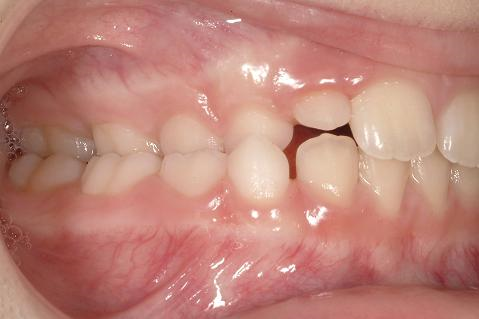

Unilateralt (enkelsidigt) korsbett är en av de vanligaste bettavvikelserna i växelbettet, med en prevalens på drygt 10 %. Bettavvikelsen innebär att överkäkens och underkäkens bredd inte passar ihop när man biter samman käkarna (fig 1). Detta betyder att underkäken glider åt sidan vid sammanbitning (så kallad tvångsföring) och orsakar korsbett på ena sidan samt deviation från mittlinjen.

Fig 1 – unilateralt korsbett